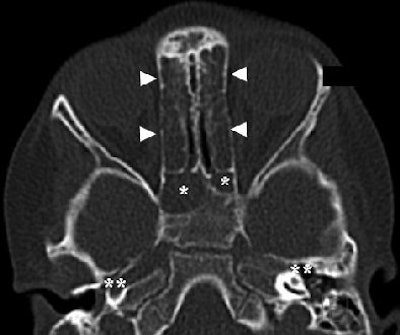

| Three-year-old girl with recurrent upper airway infections, cough, and open-mouth breathing (16-slice CT, phase 2; effective dose, 0.038 mSv). Axial image shows bilateral complete opacification of ethmoid (arrowheads) and sphenoid sinuses (asterisks) with bilateral fluid in middle ear cavities (double asterisks) (AJR 2005; 184:1611-1618). |